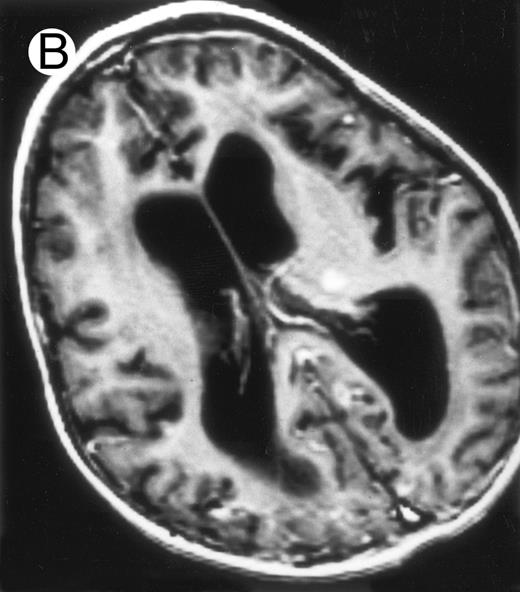

Among the nine children with initial neurological symptoms, seizures were the most frequent initial symptom in the youngest patients, whereas ataxia was found in the two oldest patients (46 and 58 months old, respectively) (Table 1). All nine patients had the same CSF abnormalities as patients with meningitis only. Eight of these nine patients had a neuroradiological study performed at the time of their first neurological symptoms (Table 1). The two most frequent lesions were focal necrosis with parenchymal volume loss and atrophy (Fig 2A and C) and white matter abnormalities (Fig 2B). Several small focal lesions with hypersignal at MR imaging that enhanced after administration of gadopentate dimeglumine (or contrast on CT scan) were also observed in two cases.

Three different aspects of brain imaging in HLH patients. (A) CT scan of a 3-month-old baby showing a large subdural effusion, several necrotic areas and hypodensities of the white matter. (B) Brain magnetic resonance of a 14-month-old boy showing large confluent areas of hypersignal in T2-weighted images. (C) Large symmetrical necrotic areas of cerebellar white matter in a 41/2-year-old girl (MRI).

Together, 19 patients had primary severe CNS disease progression or CNS relapse (Fig 1). Three of 19 had a CNS relapse characterized by meningitis only. Neurological symptoms occurred in 16 of these 19 patients (9 from the onset and 7 after the initial meningitis) (Fig 1). No clinical or neuroradiological difference was detected between the patients who developed neurological symptoms as the initial CNS manifestation or after initial meningitis (Table 1). The occurrence of these neurological manifestations marked a turning point in the evolution of the disease, as chemotherapy led to an improvement of the neurological symptoms in only three patients despite the use of intensive treatment by MTX IT. In these three patients, neurological sequelae persisted after the first symptoms and a relapse occurred within 3 to 10 months. Brain imaging was repeated during chemotherapy for four patients with progression of the CNS disease: in three patients, a severe brain atrophy developed (Fig 3A and B) and in the last patient who initially had contrast enhancement in cerebellar white matter, a cerebellum parenchymal loss was observed (Fig 2C). All of these 19 patients treated by chemotherapy only (n = 15) died during a last episode of coma and brain stem symptoms associated with a systemic hemophagocytic syndrome, 6 ± 6 months after the first neurological symptom (irrespective of the age at this first event). Four of these 19 patients were transplanted (one patient received an HLA-identical BMT, three an HLA-partially identical BMT). Median delay between diagnosis and BMT was 14 months (range, 2 to 20 months). All of these four patients died of BMT-related toxicity and/or disease progression.